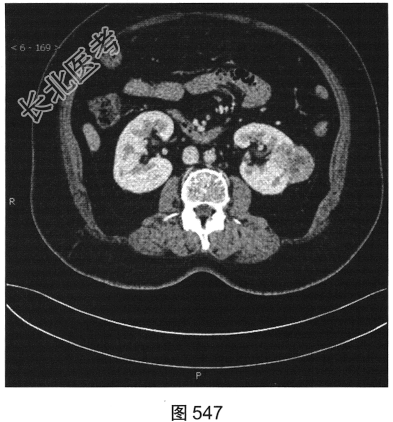

- 多项选择题3.[提示]CT平扫+增强(图545~图549):左肾下极背外侧软组织密度灶, 部分突出于肾实质外,其内可见低密度坏死灶, 增强扫描强化不均匀,平扫、皮质、实质、排泌CT值36HU、92HU、73HU、53HU。可考虑的鉴别诊断为( )

A、肾嗜酸性粒细胞腺瘤

B、出血性囊肿

C、肾血管平滑肌脂肪瘤

D、肾细胞癌

E、肾转移瘤

F、淋巴瘤